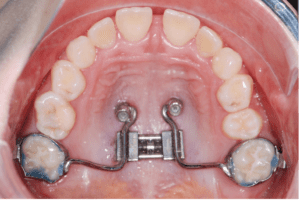

More recently, we have used mini-implants to share the load of the expansion with the anchorage teeth to reduce or eliminate the unwanted dental side effects. Wilmes et al. introduced the Hybrid Hyrax expander in 2007 using two mini-implants in the anterior palate and two (deciduous) molars (Fig. 1).7-10